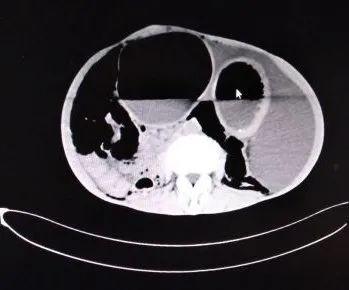

单纯性小肠梗阻(中腹部见多个阶梯状气液平面及胀气肠襻.

03 气液平征 气液平表明存在肺脓肿或带有支气管胸膜瘘的脓胸.

扩张,积气积液,立位片可见高低不 平的气液平面呈不连续的阶梯状排列

气液平面x线图片

气液平面